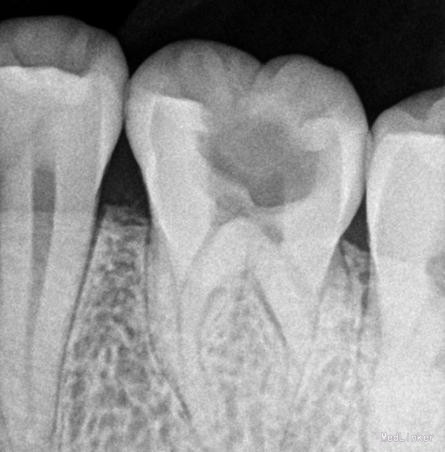

患者,男 40岁 主诉:左上后牙疼痛3天 现病史:左上后牙3天前出现疼痛,夜间痛加重,就诊要求检查

检查:#26 合面见大洞,洞内大量棕黄色腐质,探(++),冷热刺激疼痛加重,扣(—),牙龈未见异常。

诊断:#26牙髓炎 治疗计划:#26根管治疗,后期纤维桩加固嵌体保护冠修复。局部麻醉下开髓,根管预备,消毒。(近中发现mb2)